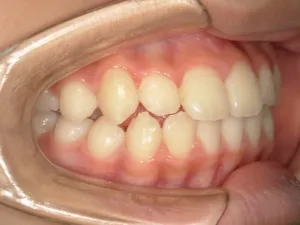

治療前①小2:8y1m 初診

| カウンセリング・診断結果 | 前歯が受け口になっていているため、適正な成長へ誘導するために前歯の咬み合わせの改善が必要なことを説明し、診断を希望されたので精密検査へ進みました。 精密検査の結果、骨格的には受け口傾向、下顎前歯の突出、上下ともアーチが小さく凸凹(叢生)が認められ、機能的には低位舌と口唇閉鎖不全があり、口元は上下唇とも突出していますがコンケーブになってないことがわかりました。 |